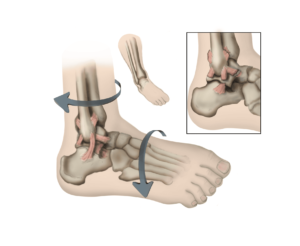

Ligaments are robust, fibrous tissues that play a vital role in connecting bones throughout the body, ensuring stability and proper alignment of joints. In the ankle, multiple ligaments work together to maintain bone positioning and provide the joint stability needed for daily activities like standing, walking, and running. Approximately 90% of ankle sprains result from an inversion injury, where the foot turns inward, primarily affecting the anterior talofibular ligament (ATFL) and the calcaneofibular ligament (CFL) on the outer side of the ankle. Less commonly, medial ankle sprains occur due to eversion injuries, where the foot turns outward, damaging the deltoid ligament on the inner side of the ankle.

An ankle sprain is an injury to one or more of the ligaments that stabilize the ankle.

The lower leg or foot can roll, or invert, leading to a sprain of the ligaments on the outside of the ankle.